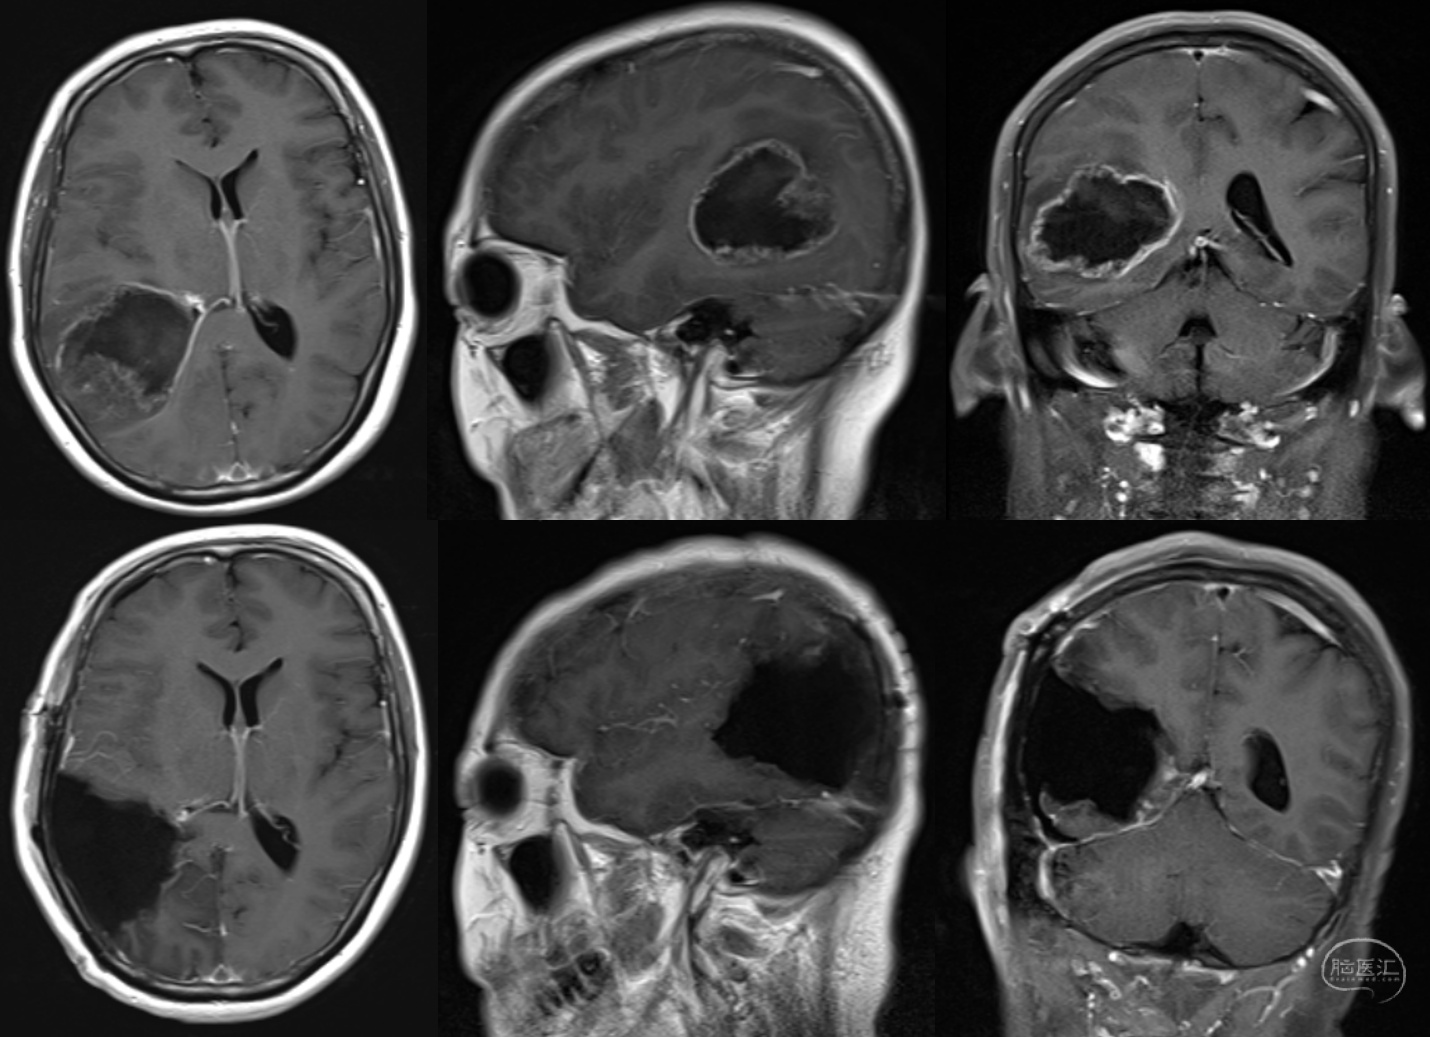

(一)左颞内侧巨大胶质母细胞瘤全切一例

患者,女,60岁,1年前出现记忆障碍伴反应迟钝,症状进行性加重,5个月前突发意识不清伴四肢抽搐1次,5天前出现头痛。

术前检查提示左颞内侧巨大占位,病灶不均匀强化,弥散明显受限。

术后CT、MRI检查提示肿瘤全切,术区出血水肿均不明显。